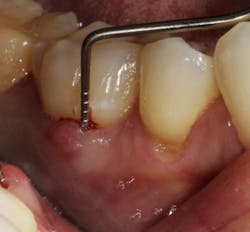

In other words, even experienced clinicians who access a root surface with flap surgery are sometimes limited in the amount of detoxification that can occur due to the depth of the defect and conventional instrumentation. (11) Further limitations with mechanical access to defects can come in the form of furcations with multirooted teeth. The diameter of the entrance to root furcation is usually smaller than the average tip of a curette, which can make access difficult (figures 1 and 1a). Molars with bone loss that includes furcations are often downgraded in prognosis due to this access difficulty. (12)

Figure 1a: Deep Class II furcation with an entrance smaller than the diameter of a curette tip